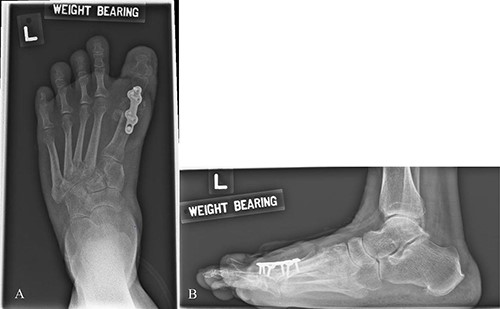

Mdm. S.N.C is a 59-year-old lady with a background of hypertension and diabetes mellitus who had corrective surgery for her left hallux valgus deformity in July 2020 (Fig. 1). This was complicated by wound dehiscence and exposure of the underlying tendon (Extensor hallucis longus) and implant (Fig. 2). An arterial duplex scan was done, which showed 70–80% occlusive disease over the proximal anterior tibial artery (ATA; Fig. 3) that likely contributed to her poor wound healing.

AP (A) and Lateral (B) X-ray the left foot. Metal implants seen over dorsal MTPJ of the 1st toe after corrective hallux valgus surgery.